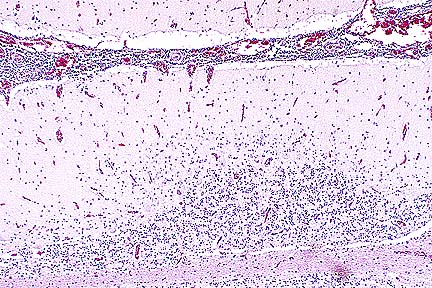

Numerous PAS-positive neuronal and glial inclusions in the cerebellum of a Maine Coon cat with tremors and seizure-like activity. (PAS, 100X, 65K)

Contributor's Diagnosis and Comments: Cytoplasmic polyglucosan inclusions (Lafora bodies) within neuronal perikarya and processes, most numerous in Purkinje cells.

In sections of brain, there are few to many basophilic to amphophilic inclusions that occur within the cytoplasm of nerve cell bodies, neuronal processes, and scattered in the neuropil. These inclusions are usually round, range in size from 2 to 10 um diameter, and occasionally have a pale center or a thin, striated halo. These Lafora-like bodies are most numerous in the cerebellar molecular layers and within Purkinje cells, but are observed in all examined sections of brain.

AFIP Diagnosis: Cerebellum, molecular and Purkinje cell layers: Polyglucosan bodies (Lafora bodies), neuronal and extracellular, diffuse, numerous, Maine-Coon, feline.